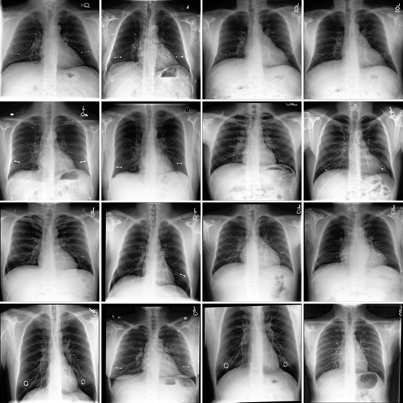

Refer to caption

Figure 2: SAE-Rad identifies clinically relevant and interpretable features within radiological images. We illustrate a number of pathological and instrumentation features relevant for producing radiology reports. We add annotations (green arrows) to emphasize the presence of each feature.

Figure 2 illustrates randomly selected monosemantic visual features from SAE-Rad. As can be seen, the SAE learns human-interpretable visual concepts despite the homogeneity and relatively small size of the dataset. These include dextroscoliosis of the spine (Fig. 2; feature 1), bilateral opacifications (Fig. 2; feature 2), unilateral pleural effusions (Fig. 2; feature 3), and the presence of instrumentation – in this case a pacemaker (Fig. 2; feature 4). In Fig. 3, we illustrate an example ‘findings’ section for a CXR with a number of pathological findings; SAE-Rad is capable of detecting multiple relevant pathologies for a given image. Like other radiology report generation systems, SAE-Rad can miss findings. However, it can also occasionally describe a relevant finding which is otherwise missing from the reference report – an example relating to the presence of a dialysis catheter is shown in Fig. 3.